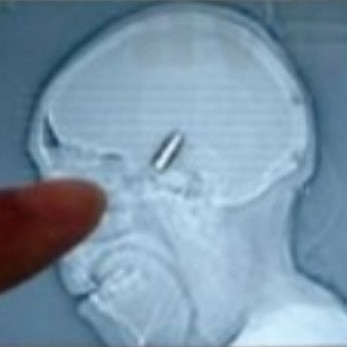

Вратар от аматьорската лига в Босна игра 90 минути с куршум в главата